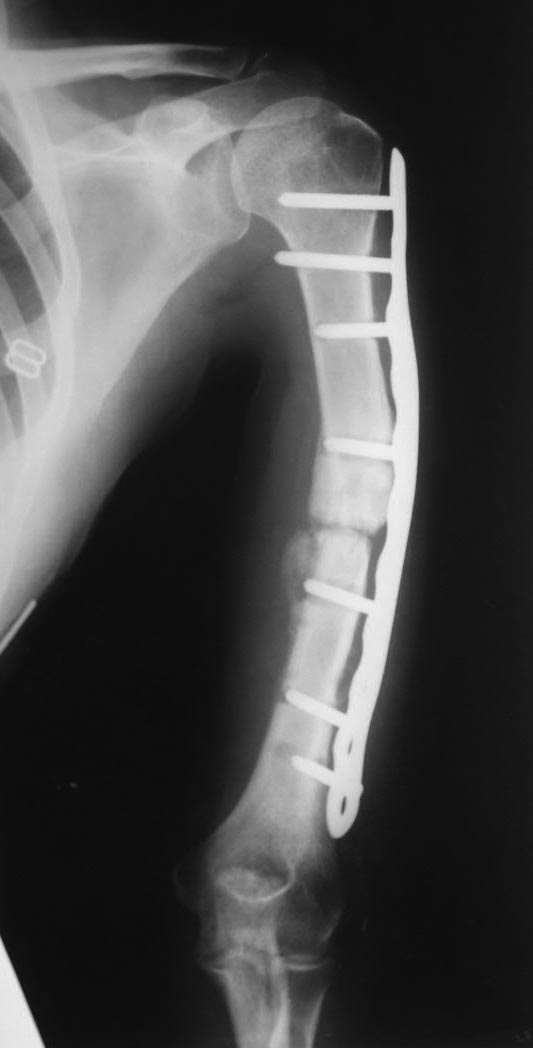

дефект-диастаз левой плечевой кости

Два года назад - перелом плеча.

Последовательно ставили три пластины. На все - отторжение металла.

Сейчас - дефект-диастаз+укорочение. Суммарный дефект около 6 см. Дырки от винтов. Инфекции нет.